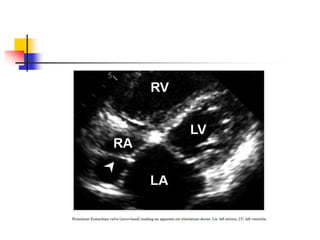

 Occasionally, prominent Eustachian valve appears to

divide RA into two chambers making apparent cor

triatriatum dexter .

 Such condition is hemodynamically insignificant in

most adults because the septation by Eustachian

valve is generally incomplete.